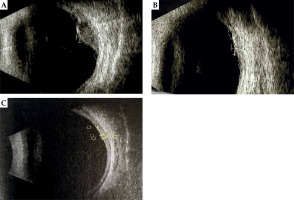

Fig. 1

Ultrasound images of the melanoma before (A), two (B), and four (C) years after the treatment, showing a part of the tumor located in the posterior pole and in the area of the equator

In 5 patients (56%) treated with the ophthalmic applicator displacement method, a positive result, i.e., local control of the tumor was achieved. In the remaining 4 cases (44%), a local recurrence developed. Within the follow-up period (range, 6-37 months; mean, 17.5 months), 4 patients underwent enucleation: 3 cases due to tumor progression and 1 due to radiation complications, despite the positive results of local treatment. One patient with recurrence was qualified for a secondary 106Ru brachytherapy with transpupillary thermo-therapy. As a result of the second treatment, a positive local result of the therapy was obtained. In the 4 remaining patients with positive local results after the first treatment, no recurrence of uveal melanoma was observed within the follow-up period (range, 7-62 months; mean, 23.1 months). Results presented in Figures 1 and 2 show the positive effects of treatment of the patient, who has been under control for the longest time, i.e., over 6.6 years.